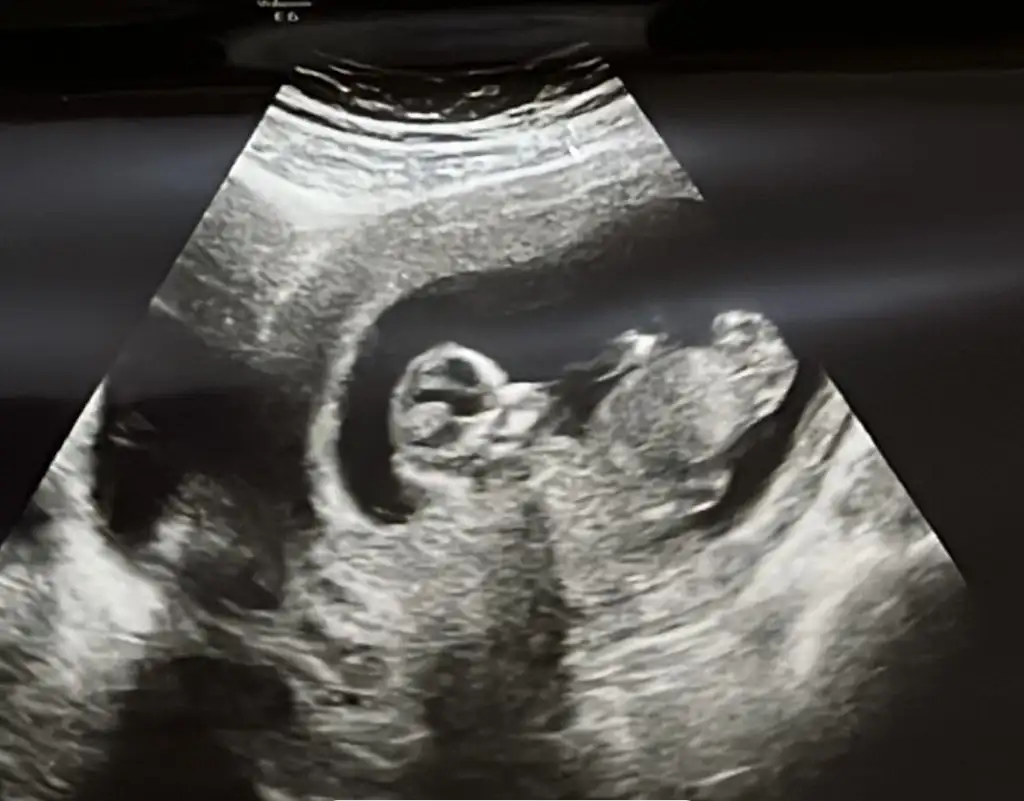

Bana bir daha yorum yapsana bebeğim yaaa 12+1 di bu hafta gttiğimde önde çıkmıştı günü 5 gün kdr. Normalde 11+3 tük Z Zzzzz00

Eklentiler

• 1675250561533.webp

15,6 KB · Görüntüleme: 72

• 1675250561567.webp

13,9 KB · Görüntüleme: 71

• 1675250561601.webp

15,2 KB · Görüntüleme: 65

• 1675250561637.webp

12 KB · Görüntüleme: 67